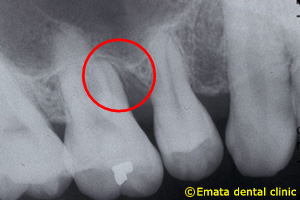

根分岐部病変

(根が分岐している奥歯に生じた歯周病)

の治療

~専門医・指導医による歯周病治療3~

治療の概要

根分岐部病変は、歯根が2本以上ある歯の根分岐部まで進行した歯周病で、歯石除去が難しくブラッシングもしにくい場所のため、症状が出にくく治療が難しいのが特徴です。歯周病を制するには根分岐部病変を制する必要があり、進行した場合は抜歯の選択肢が検討されることも少なくありません。

治療の流れ

さっさと抜いてインプラント、ではなく、根分岐部病変をどう考えてどう生かすかが歯周病専門医の姿勢や力量です。

治療例の紹介